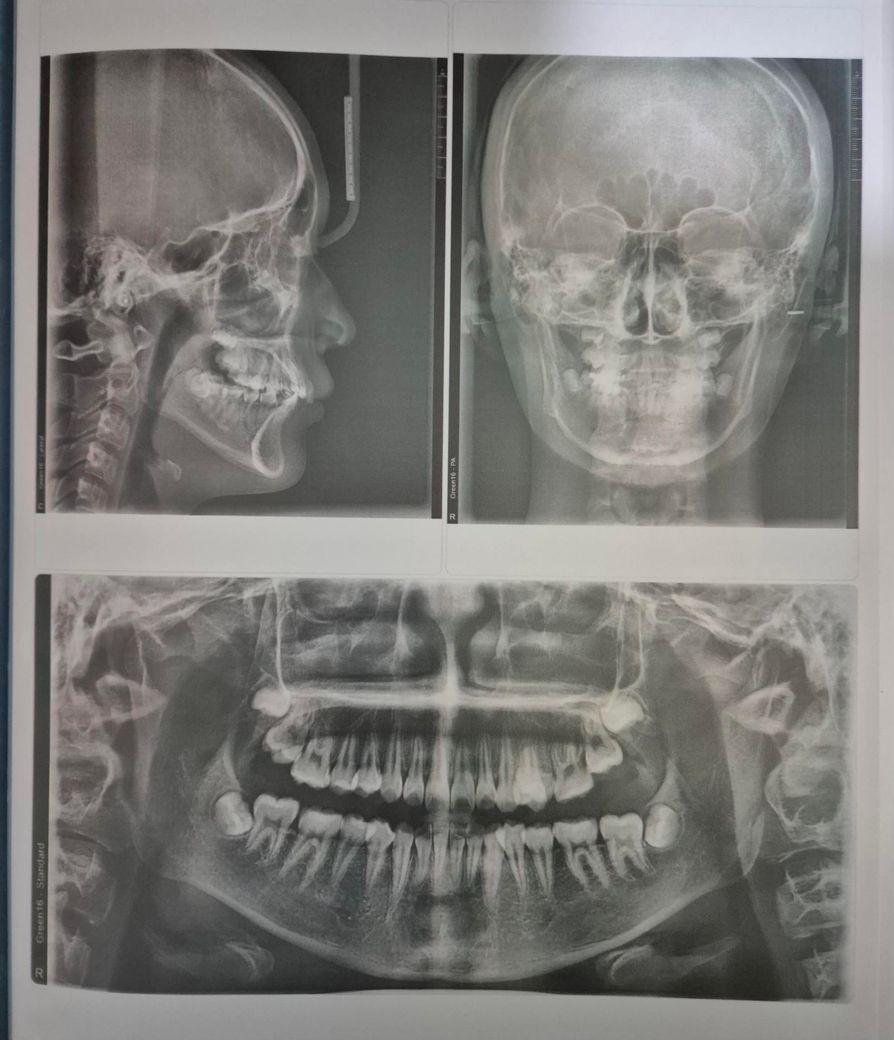

현재 치아교정 중인데 발치 문제로 병원을 옮겨야하나 걱정입니다

현재 초등학교 6학년 아이 교정중인데요

발치 여부로 트러블이 있어요

전 발치없이 진행하자 하고 선생님은 치아 2개 발치해야 한다 하셔서요

원래 돌출이 심한상태도 아니었기에 어금니 발치시 입이 너무 들어가 보일 것 같아 전 비발치를 원하고 있는 상태입니다

교정전 사진, 교정기 중인 사진, 치아사진 올립니다

꼭 발치가 필요한 상태인지와

병원을 전원 할 경우의 문제 등 답변부탁드려요.

교정치료 중에도 생각보다 치아이동이 원활하지 않은 경우, 필요공간이 확보되지 않는 경우 발치 계획이 추가될 수 있습니다